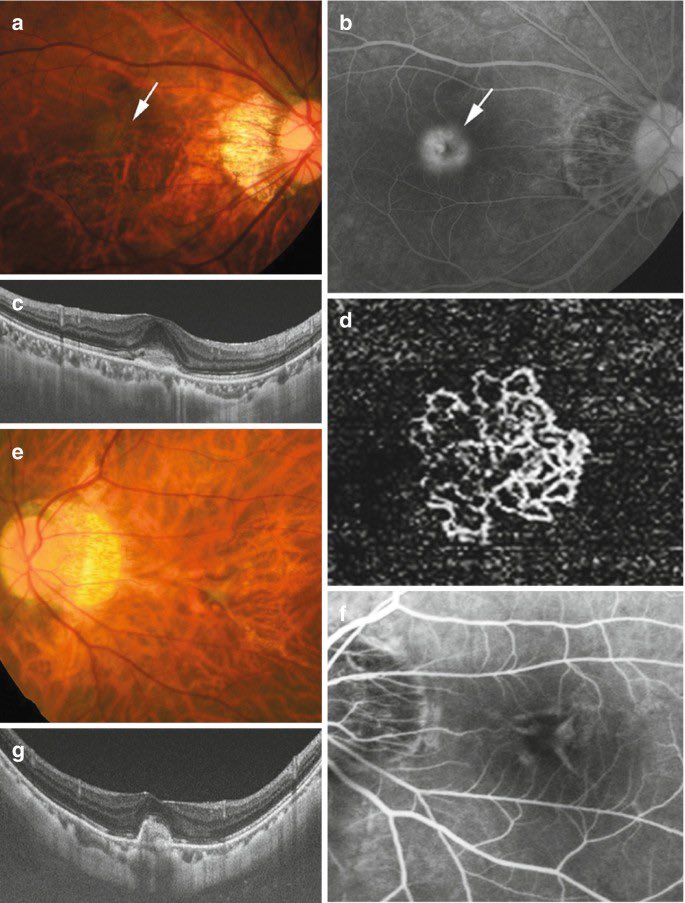

احد المضاعفات الخطيرة المحتملة هي نمو اوعية دموية من مشيمة العين الى الشبكية، وتسبب ضعف الرؤية وتموجها

وتعتبر حالة طارئة تستدعي العلاج الفوري عن طريق حقن العين بعلاج والمتابعة، استجابة الاوعية الدموية للحقن في حالات قصر النظر العالي تعتبر ممتازة وسريعة في غالب الحالات